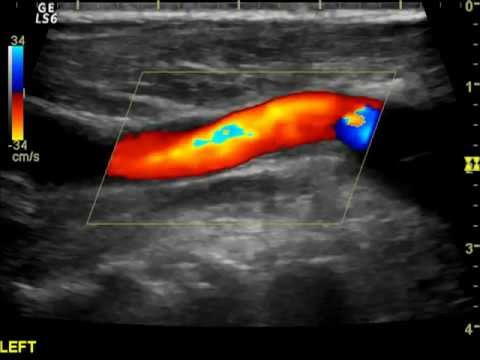

Hellow guys, Welcome to my website, and you are watching Carotid-Carotid-Subclavian Bypass with Vertebral Artery Transposition (Lumsden, MD, Andraos, MD). and this vIdeo is uploaded by Houston Methodist DeBakey CV Education at 2021-07-08T07:25:58-07:00. We are pramote this video only for entertainment and educational perpose only. So, I hop you like our website.